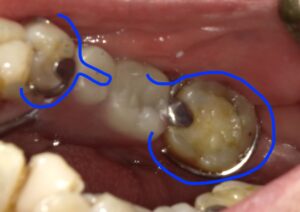

画像の左がエーカースクラスプ、右がバックアクションクラスプです。

青の線のようにリング状になっています。